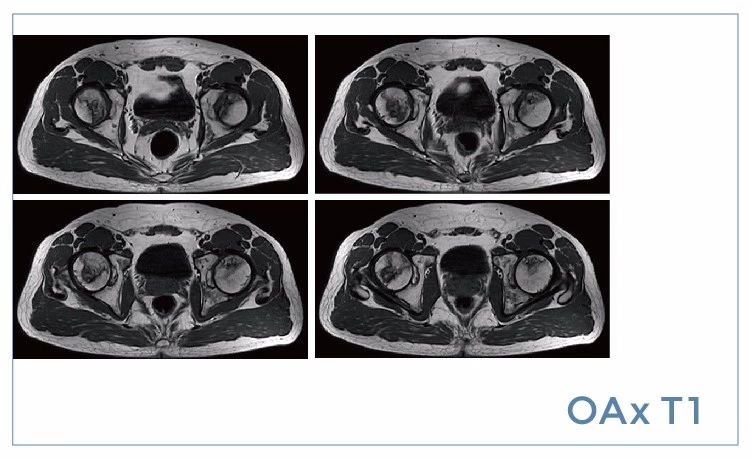

【朗润影像档案】磁共振影像病例分享(编号20190802)